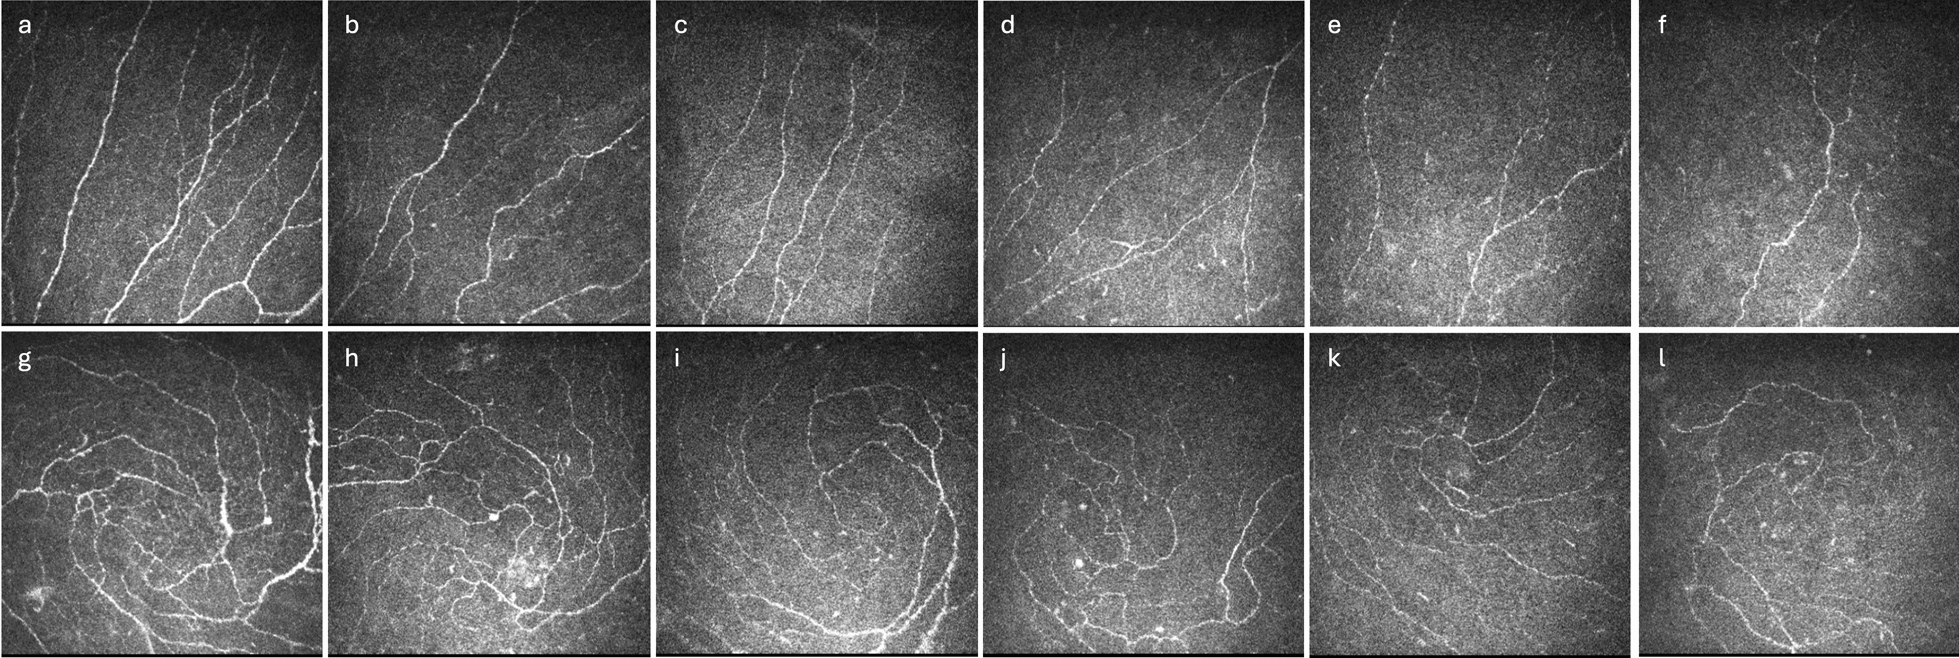

Methods: This cross-sectional study included a total of 385 healthy controls and 663 patients with DM. Metrics for corneal nerve and epithelial cells were evaluated using in-vivo confocal microscopy (IVCM). Corneal nerve and epithelial cell parameters were quantified and compared between patients with and without obesity and across six different body mass index (BMI) categories. Multivariable regression analyses were conducted to determine the association between corneal nerve metrics and BMI in patients with DM.

Results: Of the DM participants, 162 (25.4%) had obesity. Compared to the non-obese group, patients with obesity had significantly lower corneal nerve fiber density (CNFD, P < 0.0001), corneal nerve fiber length (CNFL, P = 0.002), and corneal nerve branch density (CNBD, P = 0.005). Analyses across different BMI categories showed a progressive decline in corneal nerve parameters including CNFD (P < 0.0001), CNFL (P < 0.0001), CNBD (P < 0.0001), corneal nerve fiber total branch density (P = 0.003), corneal nerve fiber area (P = 0.04), and corneal nerve fiber fractal dimension (P = 0.02) with increasing obesity severity. Multivariable regression analyses demonstrated that lower CNFD (β: - 0.21, 95% CI: - 0.29 to - 0.13, P < 0.0001), shorter CNFL (β: - 0.12, 95% CI: - 0.17 to - 0.07, P < 0.0001), and lower CNBD (β: - 0.17, 95% CI: - 0.30 to - 0.04, P = 0.01) were significantly associated with BMI after adjusting for confounders. There were no significant differences in the corneal epithelial parameters between the obese and non-obese groups.

Conclusions: General obesity, specifically higher BMI, adversely affects corneal nerve health in individuals with DM. Evaluation of corneal nerves and resultant keratopathy should be considered in patients with DM and concomitant obesity.